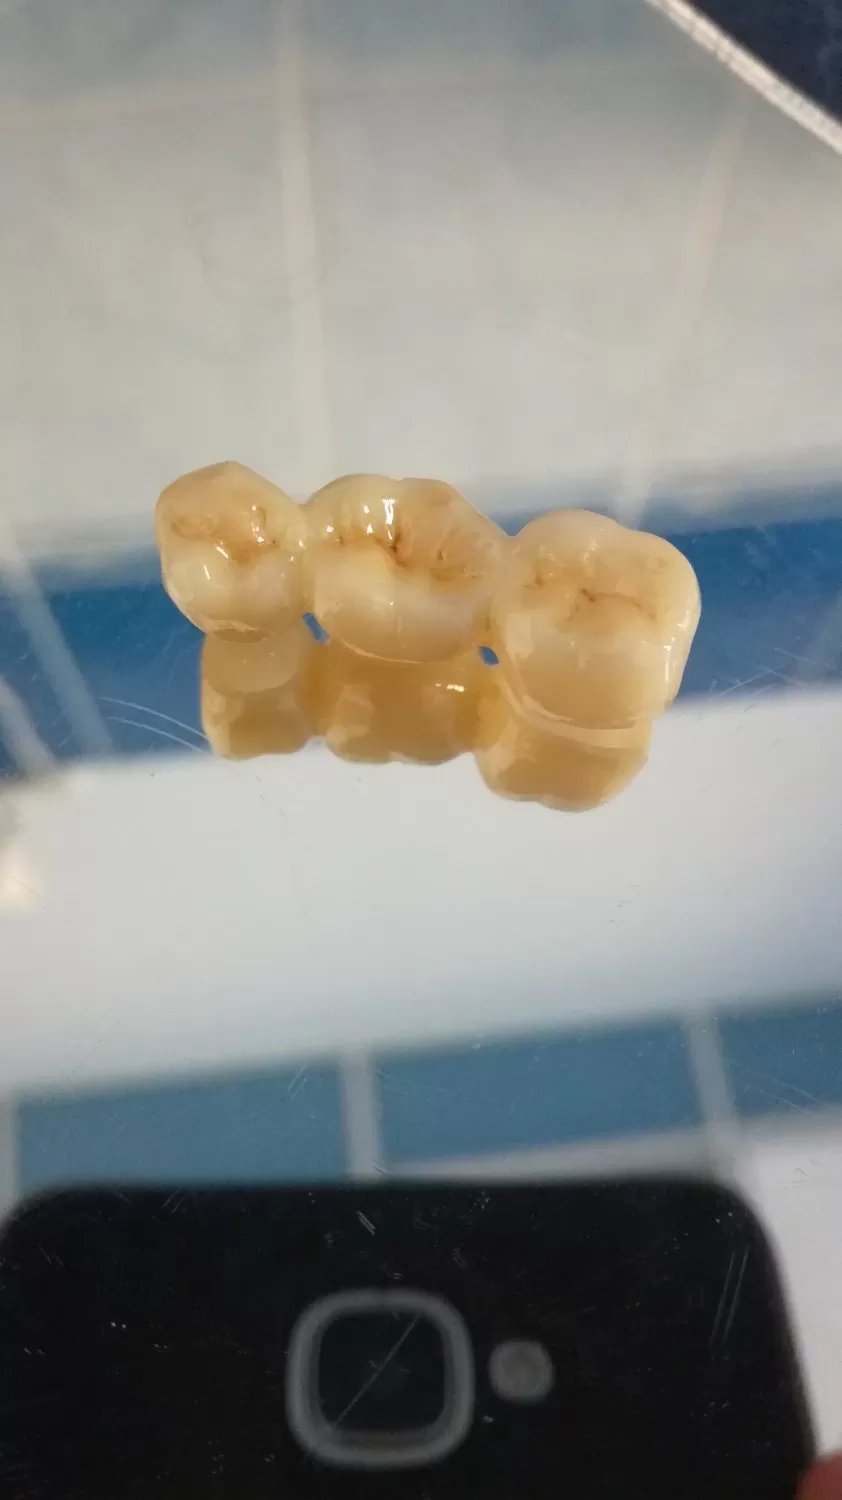

С лета 2018 лечусь в клинике Лигадент у доктора Трошян Тиграна Гамлетовича. За это время доктор восстановил мне все зубы, при лечении которых ранее были допущены, мягко говоря, ошибки. Произвел впечатление очень ответственного, грамотного, образованного специалиста с большим опытом, Это настоящее счастье, когда с тобой работает профессионал такого уровня! Далее мне поставили читать далее